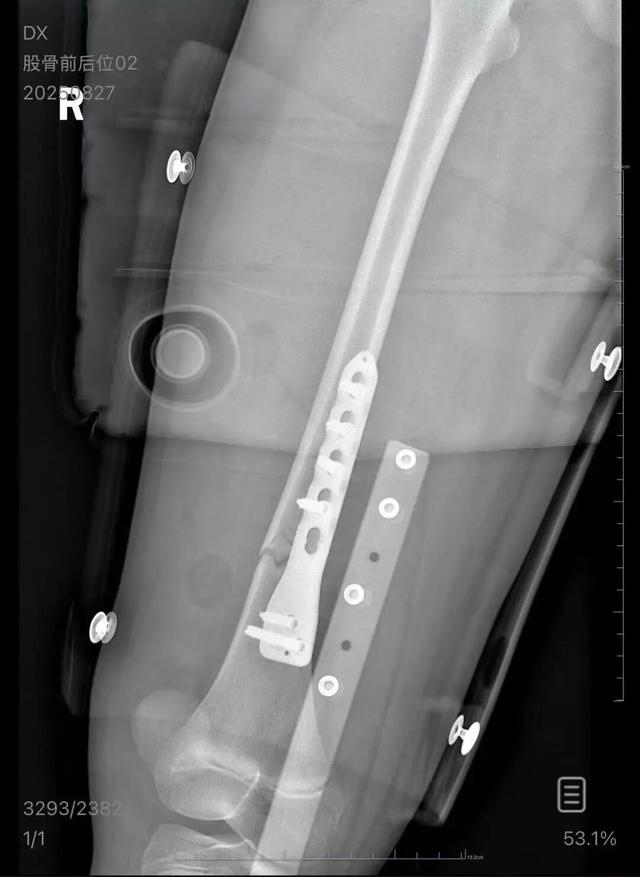

▲朱女士女儿手术后拍的X光片 受访者供图

朱女士向记者出示的医院病历显示 ,8月24日凌晨,朱女士的女儿到医院就诊 。医院诊断朱女士的女儿右股骨骨折,需要住院进一步治疗。

朱女士告诉记者 ,医疗费加上护工费已经花费了5万多元,“而且在出院以后,医生说因为植入了钢板 ,后续孩子可能会有后遗症,最有可能出现的是长短腿,让我们去做康复治疗 ,这就面临着另一笔费用。”